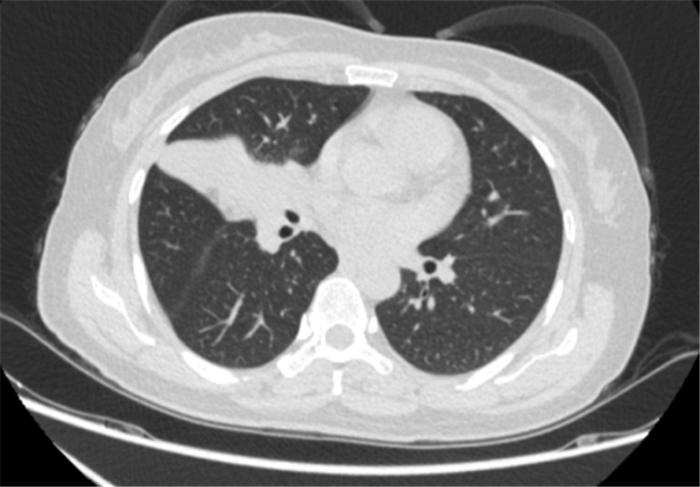

经过4个周期的治疗后复查发现:李女士的病灶明显缩小,实现了降低肺癌分期。

免疫联合化疗新辅助治疗4周期后胸部CT